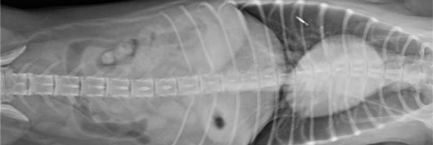

흉복부 방사선검사와 필요할 경우 초음파검사

마취를 하는데 문제가 될 수 있는 심장질환, 호흡기 질환, 소화기 질환, 종양 유무를 확인하기 위해서 흉부와 복부 방사선 촬영 검사가 필요합니다.